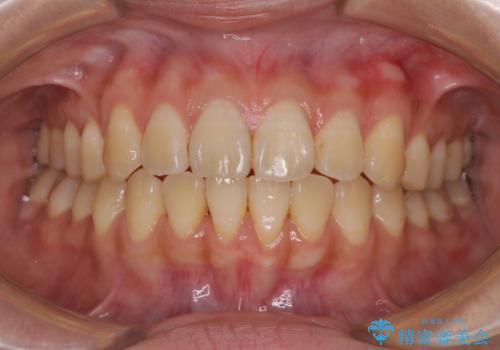

舌の突出癖による開咬と前歯の突出 インビザライン矯正治療

- 上下前歯の非接触と叢生を気にして来院された患者様です。

開咬の改善はインビザラインの最も得意とするところであるため、インビザラインを用いて矯正治療を行うこととしました。

治療開始直後に上顎前歯に激しい痛みが発現し、矯正治療を休んだり、マウスピースの装着時間を短くしたりと工夫をしましたが、残念ながら治療途中で失活していることが分かりました。

矯正治療の途中で前歯の根管治療とオールセラミッククラウンによる補綴治療を行い、その後インビザライン1セットを用いて細かい部分を仕上げました。